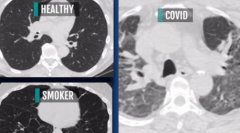

888大奖88pt88:研究:新冠患者肺部伤疤比吸烟严重